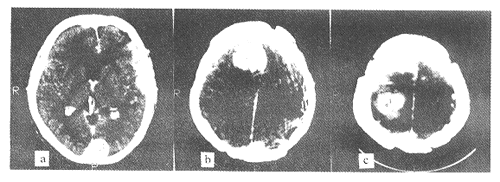

患者,女,35岁。双上肢抽搐反复发作2年,于1997年10月24日入院。体检:神清,对答切题,检查合作,双瞳孔等大0.25 cm,对光反应灵敏,双眼球活动不受限,无眼震,视力正常,左眼球外突Ⅱ°,双眼底视乳头轻度水肿,两耳听力下降,双上肢肌力Ⅴ°,肌张力正常,两下肢肌力Ⅰ°,肌张力低,病理征阴性。两侧额颞顶头皮多处手术疤痕,背部正中T7~10棘突皮肤疤痕一处,上腹部与腿部皮肤有数处牛奶咖啡色素斑。患者在1982年5月~1990年5月先后5次行大脑凸面和鞍结节脑膜瘤切除术,1985年10月左听神经瘤切除,1993年4月脊髓T9~12神经纤维瘤切除,术后双下肢截瘫,大小便尚能控制。追问患者既往无头部外伤史,家庭中无类似病史,其母亲在怀孕期曾有二氧化铀接触史。1997年10月11日头颅CT显示:左枕、右额及右顶脑表面分别三个球形高密度肿瘤阴影,增强后肿瘤密度明显增高,右额顶见片状水肿区,中线轻度左移。诊断为多发性脑膜瘤(见图1)。入院后全麻下分别作右额、右顶骨瓣开颅,术中见右额、顶区长自硬脑膜内层分别为4 cm ×4 cm ×4.5 cm、4 cm × 4 cm ×3.5 cm 肿瘤2个,小如黄豆肿瘤10多个,粟粒大小肿瘤不计其数,边界清楚,呈灰白或淡黄色,血供丰富,质韧,与脑膜粘连较紧。予以肉眼全切除。病理报告为多发性脑膜瘤,细胞生长活跃。术后恢复良好,2周后出院。

图1 1997年10月11日第8次手术前的CT复查影像:左颞、左枕、右额顶、右顶等部位的脑膜瘤病灶